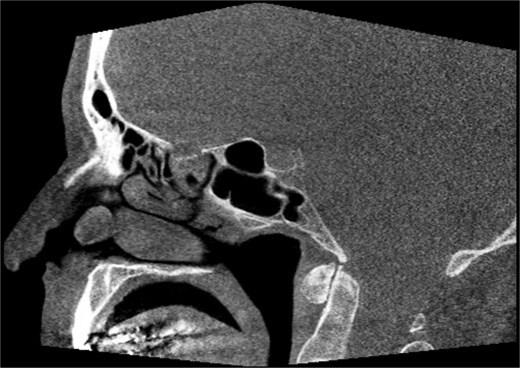

A 67-year-old male presented to our outpatient office with complaints of increasing bouts of right sided nasal bleeding for the preceding twelve months. He had been able to control the epistaxis with pressure and oxymetazoline nasal spray; however, a recent Emergency Room visit for persistent nasal bleeding prompted a referral to our office. The patient denied nasal trauma or other sinonasal problems in the past or present. He was not taking any anticoagulant or antiplatelet therapies. Nasal endoscopy revealed a soft, pale, non tender mass on the caudal end of the right inferior turbinate. Coagulated blood was noted over the anterior portion of this mass, without any vascular prominence or bleeding appreciated over the septal wall. This indicated the nasal mass was the site of recurrent epistaxis. Non-contrast computed tomography (CT) of the sinuses (Figs 1 and 2), showed a soft tissue prominence at the same area seen on endoscopy (Fig. 3).

Sagittal non-contrast CT scan images of soft tissue lesion on right inferior turbinate.